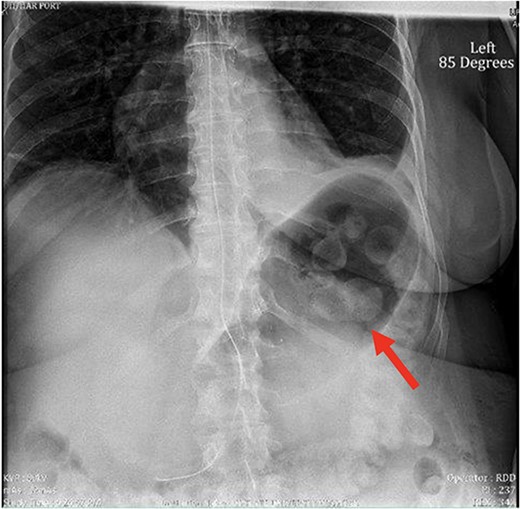

Despite the insertion of the NGT yielding 1500 cc output in 24 hours, the patient continued to experience severe abdominal pain. Urgent abdominal and pelvic computed tomography (CT) scans were taken, as seen in Figs 2–4. The CT scans showed gastric distension and the spleen positioned anteriorly in the right upper quadrant. Consequently, the decision was made to promptly bring the patient to the operating room for a diagnostic laparoscopy with plan to detorse the spleen.

CT of the abdomen and pelvis (sagittal slice) showing gastric distention and the spleen positioned anteriorly.